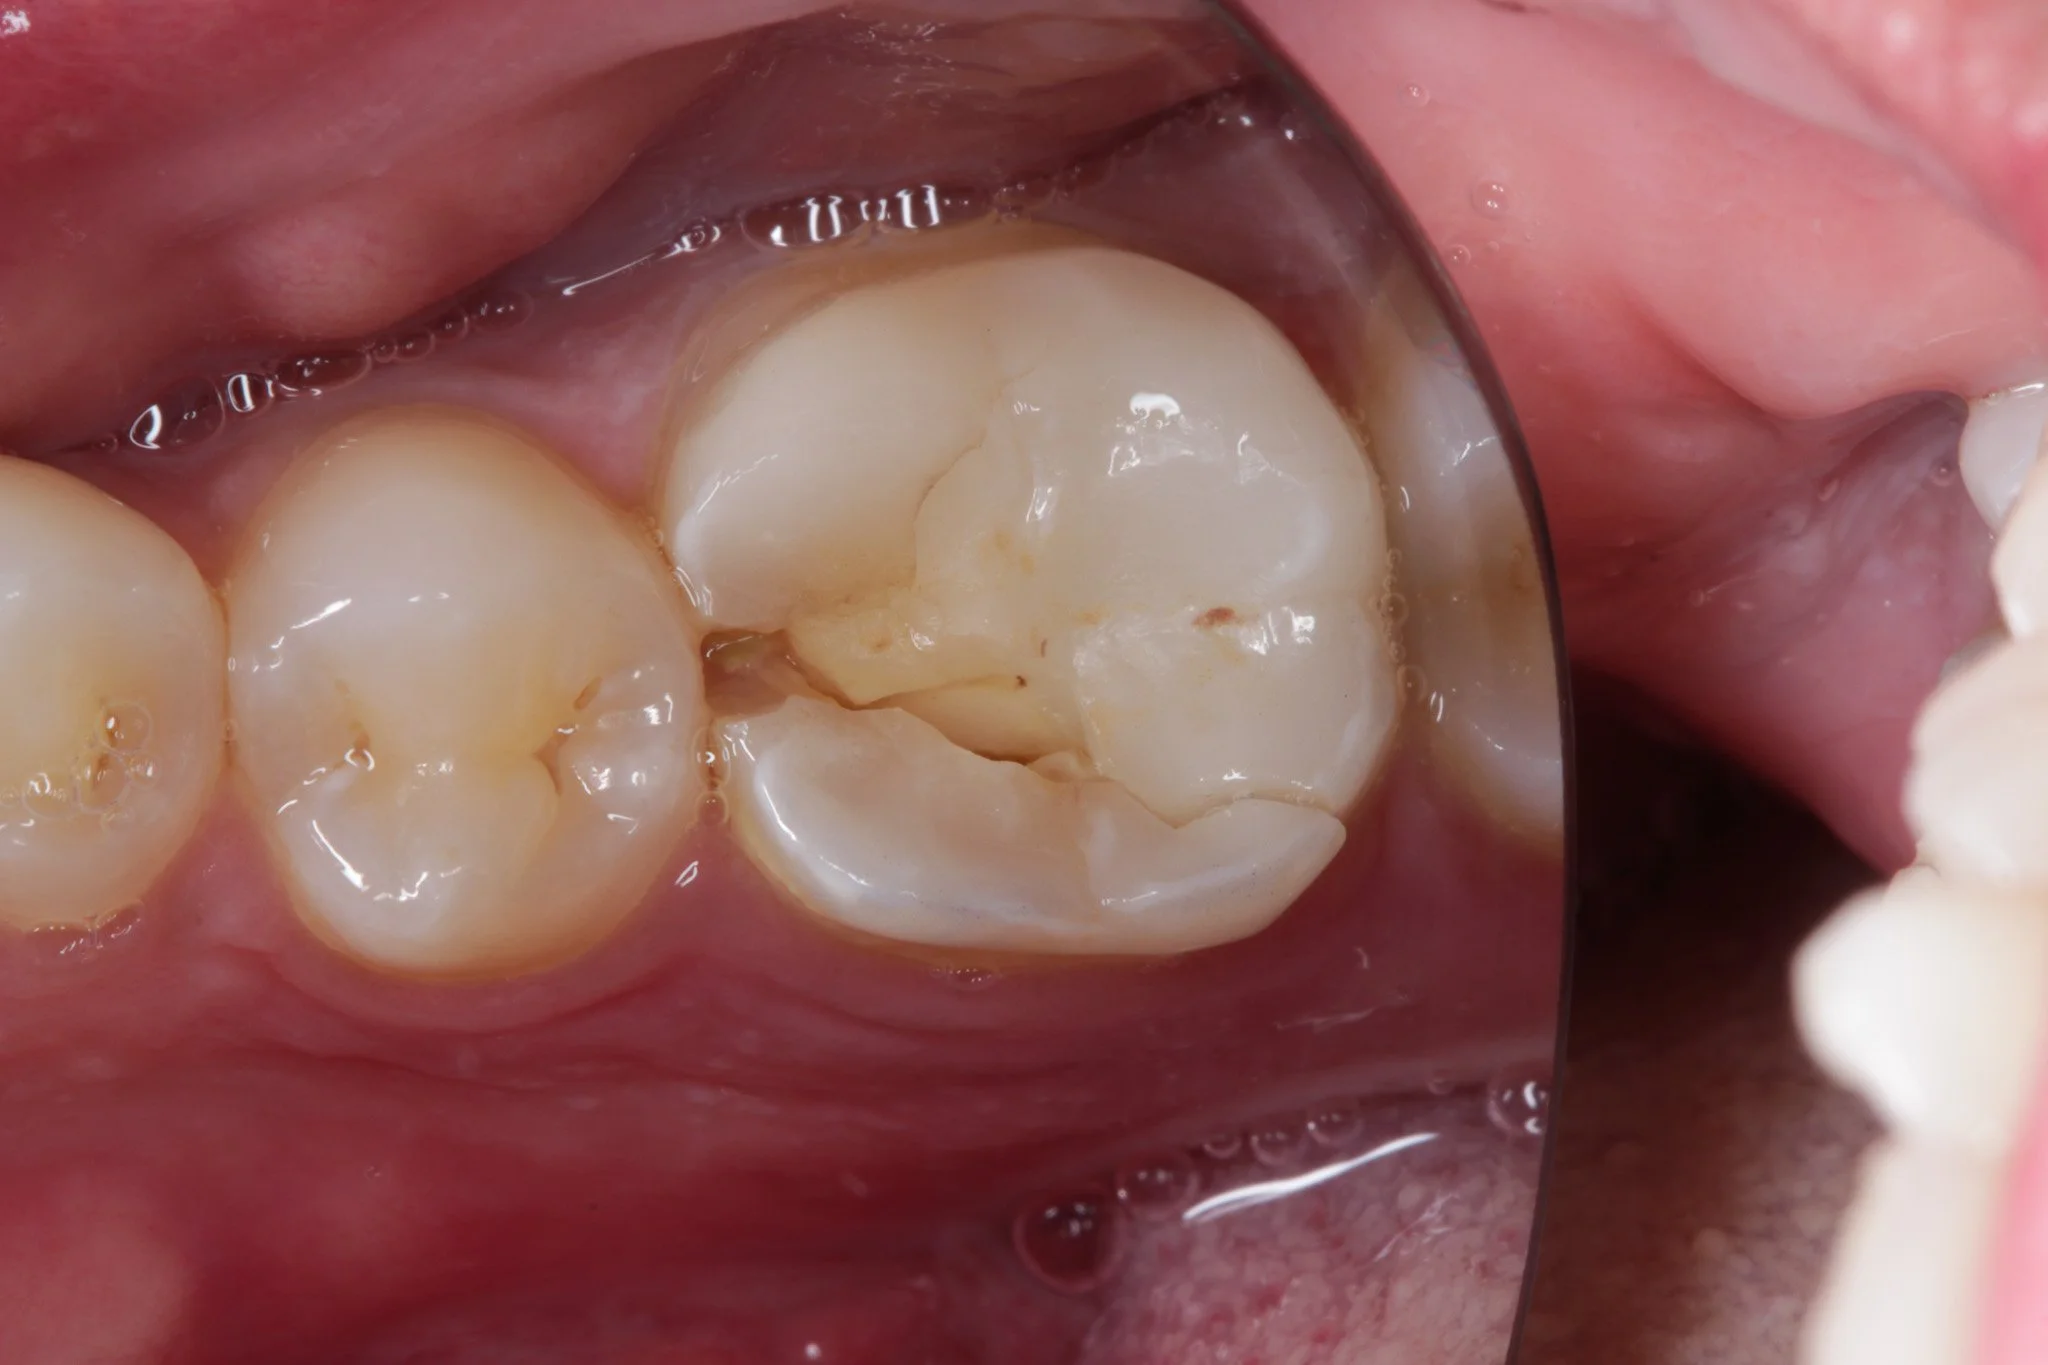

A broken filling, left untreated and now the tooth has fractured

• Fractured fillings - This is when part of the filling breaks under pressure. It might be a small chip or a larger section missing.

• Loss of structural integrity - The filling is no longer properly supporting the tooth. This increases the risk of further fracture, sometimes of the tooth itself.

Essentially is a broken filling is not repaired, the tooth around it can break or the decay can get deeper leading to a bigger filling or worse, nerve death in the tooth.